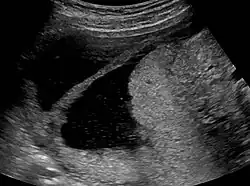

La historia del acontecimiento del embarazo seguido por la dilatación y el legrado liderizado por la amenorrea secundaria o a la hipomenorrea es común. La histeroscopia es el estándar de oro para el diagnóstico. 3 La proyección de sonohisterografía o histerosalpingografía podría revelar el grado de la formación de la cicatriz. El ultrasonido no es un método confiable de diagnosticar el Síndrome de Asherman. Los estudios de la hormona muestran los niveles normales constantes con la función reproductiva.